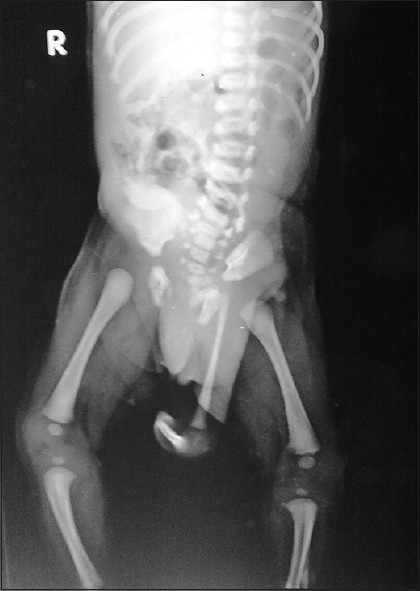

6. Polimelie

Sursa: Wikimedia Commons

Deşi uneori ne dorim să ne fi născut cu un membru în plus astfel de cazuri există, însă nu sunt deloc fericite. Polimelia este un sindrom în care persoanele se nasc cu membre în plus. Aceste membre sunt deseori nedezvoltate complet. Deşi afecţiunea apare deseori la animale, în cazul oamenilor este rară. Polimelia este clasificată în funcţie de zona în care se localizează membrul în plus. Atunci când este ataşat capului se numeşte cefalomelie, când este ataşat oaselor din zona spatelui poartă denumirea de notomelie şi toracomelie, atunci când sunt ataşate toracelui. Polimelia poate apărea şi din cauza separării incomplete a gemenilor. Operaţiile chirurgicale pot fi efectuate pentru îndepărtarea membrului în exces.